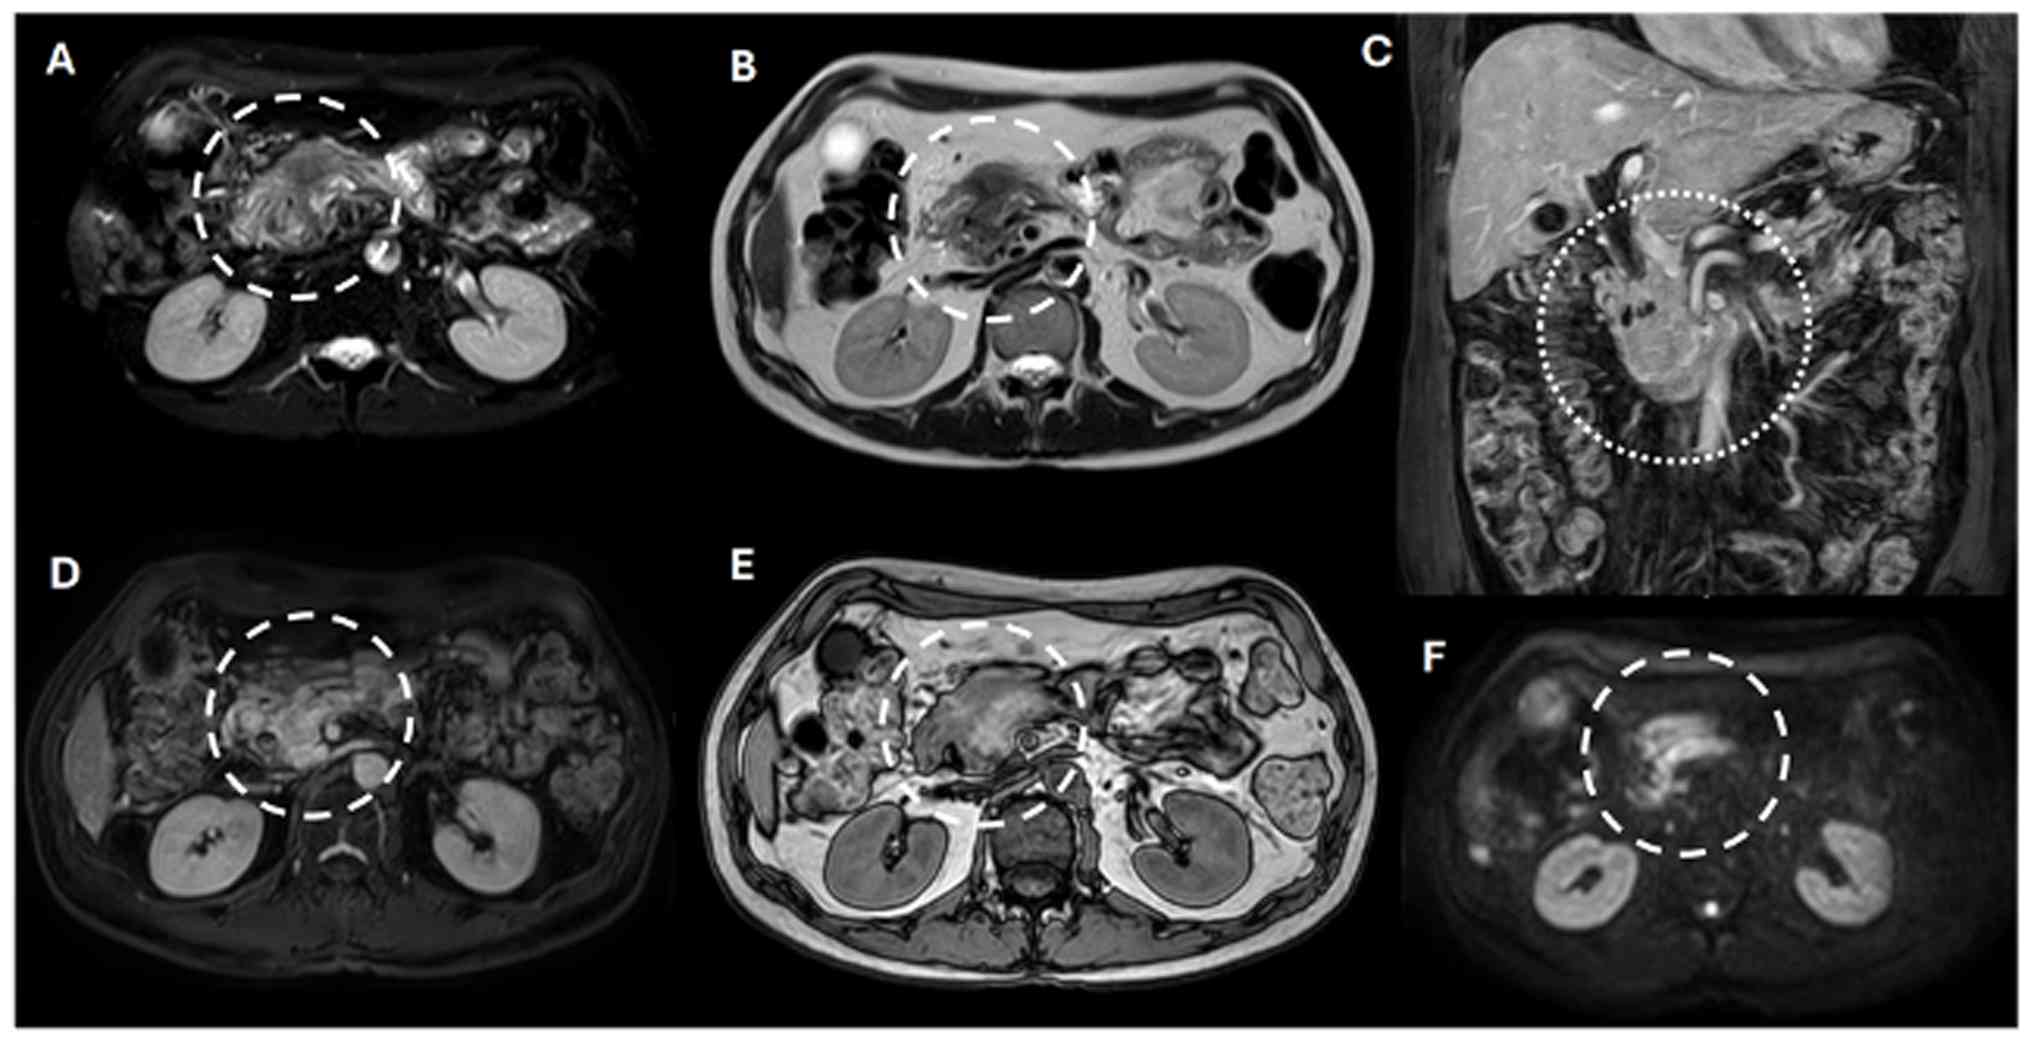

Radiological assessments indicated that the lesion in the initial portion of the duodenum lacked a discernible division plane, resulting in dilation of the central pancreatic duct and mild tail atrophy. Vascular structures, including the celiac trunk and superior mesenteric artery, appeared to maintain a division plane with the neoplasm (Fig. 2A). PET-CT revealed three focal hypodense liver lesions in segments VI, IVa, and II, all without metabolic activity (Fig. 2A). One lesion was suspicious for metastasis on PET-CT (Fig. 2B, dotted circle) and was subsequently confirmed on MRI, which demonstrated ring-like enhancement following gadolinium administration on ADC-weighted imaging (Fig. 2C, dotted circle). Several focal hepatic lesions with a non-suspicious appearance, such as hemangiomas, were also noted (Fig. 3). A mass was identified in the head of the pancreas (Fig. 3A, dashed circles), exhibiting perivascular invasion that compromised the superior mesenteric artery, inferior vena cava and abdominal aorta (Fig. 3C, dotted circle). The lesion appeared hyperintense on T2-weighted images (Fig. 3A-C, circles). Dixon-weighted sequence post-gadolinium administration demonstrated heterogeneous enhancement, which was highly suggestive of an aggressive neoplastic process (Fig. 3D, dashed circle). The out-of-phase image from the dual fast-field echo sequence displayed a heterogeneous signal intensity, indicating a hemorrhagic component and/or associated vascular changes (Fig. 3E, dashed circle). Furthermore, restricted diffusion of water molecules was observed on high-value diffusion-weighted imaging, supporting this diagnosis (Fig. 3F, dashed circle). Collectively, these imaging findings confirmed the diagnosis of an unresectable PDAC (T4N0M1; Grade IV).

Abdominal MRI of early-onset of ductal

pancreatic adenocarcinoma. (A) A lesion is visible in the

pancreatic head (dashed circles), demonstrating signs of

perivascular invasion. (A-C) The mass appears hyperintense on

T2-weighted images. (D) A Dixon-weighted sequence with gadolinium

contrast reveals heterogeneous enhancement. (E) The out-of-phase

image from the dual fast-field echo sequence shows heterogeneous

signal intensity, suggestive of a hemorrhagic component. (F)

Vascular involvement is evident along with restricted diffusion of

water molecules on high-b-value DWI, consistent with malignancy.

MRI, magnetic resonance imaging; DWI, diffusion-weighted

imaging.

Figure 3

Abdominal MRI of early-onset of ductal pancreatic adenocarcinoma. (A) A lesion is visible in the pancreatic head (dashed circles), demonstrating signs of perivascular invasion. (A-C) The mass appears hyperintense on T2-weighted images. (D) A Dixon-weighted sequence with gadolinium contrast reveals heterogeneous enhancement. (E) The out-of-phase image from the dual fast-field echo sequence shows heterogeneous signal intensity, suggestive of a hemorrhagic component. (F) Vascular involvement is evident along with restricted diffusion of water molecules on high-b-value DWI, consistent with malignancy. MRI, magnetic resonance imaging; DWI, diffusion-weighted imaging.